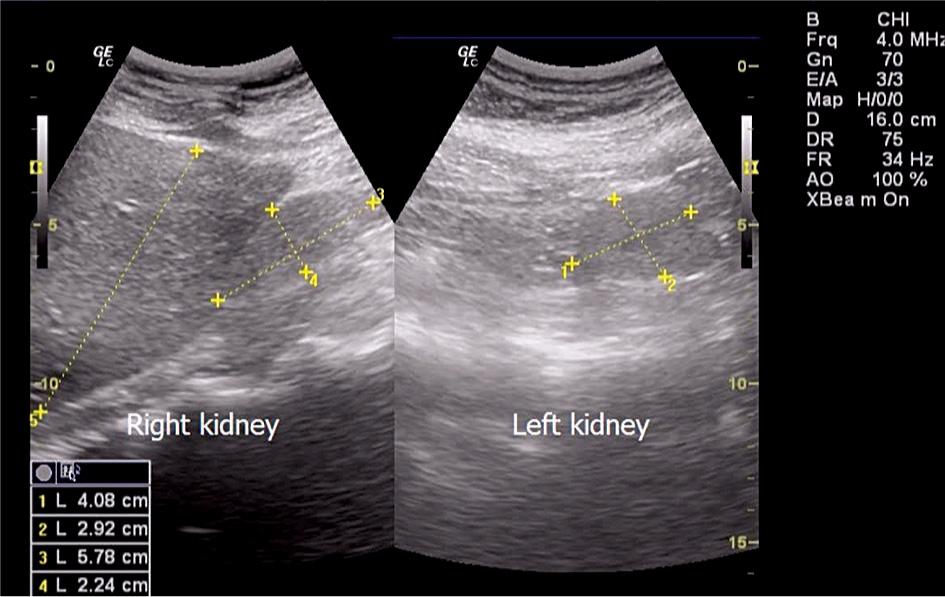

Bilateral kidney hypoplasia.